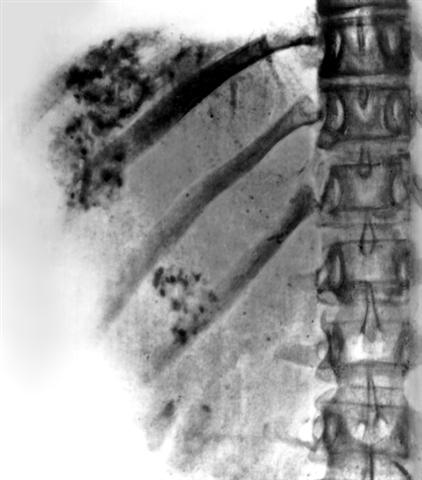

Рис. 2. Обзорная рентгенограмма области печени при альвеолярном эхинококкозе (прямая проекция): мелкоочаговые обызвествления в виде «известковых брызг» в зоне паразитарных узлов.